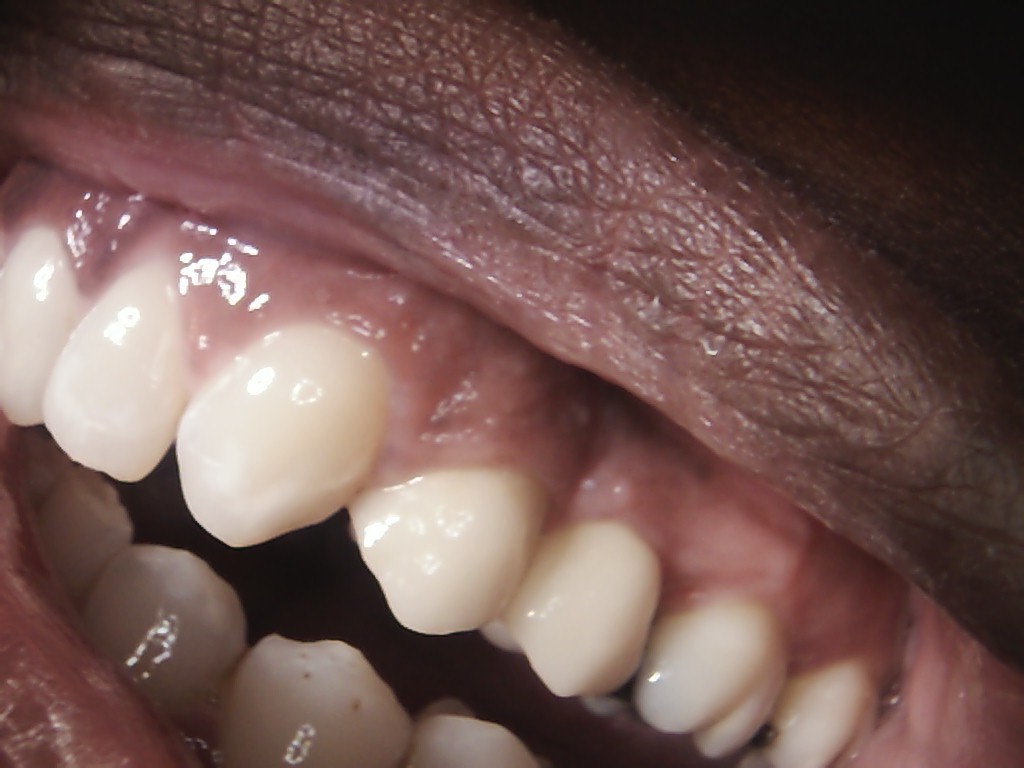

Examples of our work.

Single front tooth case